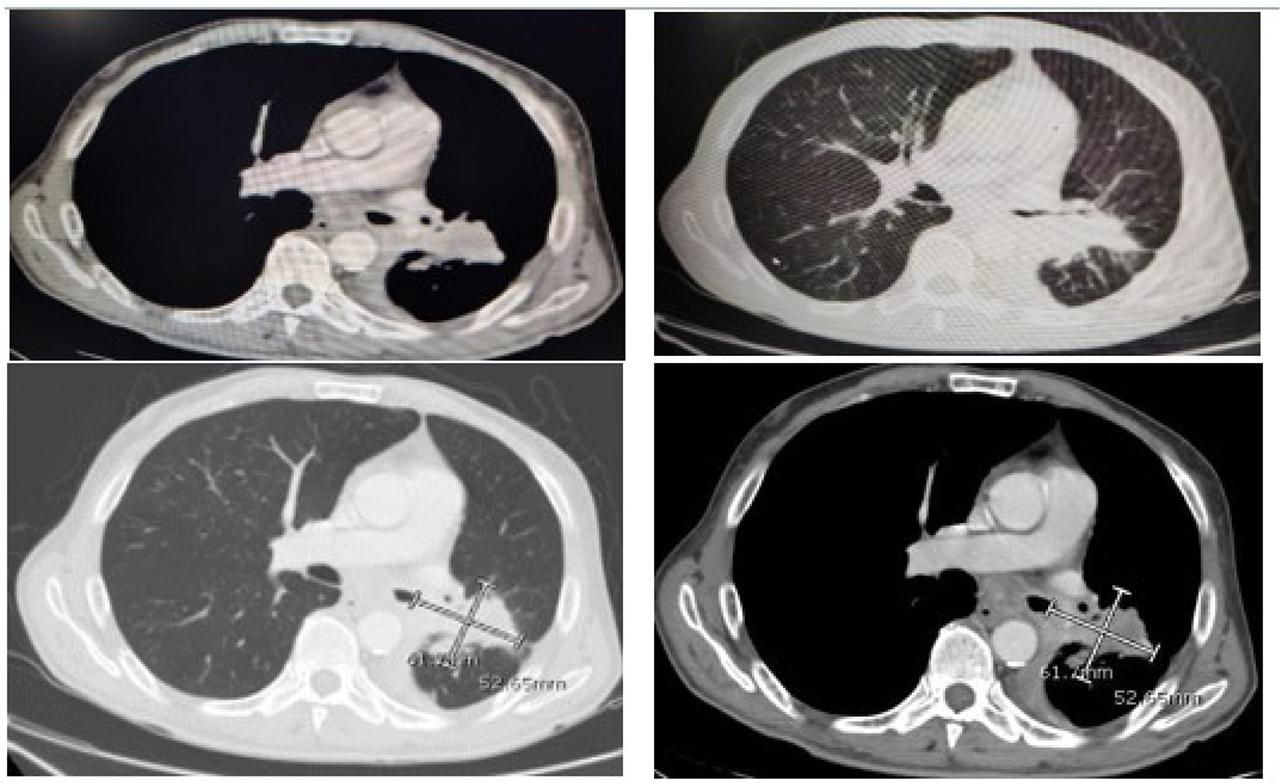

Chest computed tomography (CT) scan: Speculated soft tissue mass seen on the left main bronchus, measuring about 6.1 × 5.2 cm (measured lesion) and associated with subcarinal ln and minimal pleural effusion.